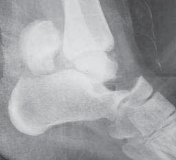

FIG 1 • Hawkins classification of talar fractures. A. Type I: disruption of anterolateral perfusion. B. Type II: medial perfusion intact. C. Type III: all D sources of blood flow injured. D. Type IV: dislocation of all articulations. 1. In the type III injury, the transverse fracture of the talar neck is associated with dislocation of the talar body. The incidence of osteonecrosis of the talar body is 50% to 100%. All major perfusion to the body of the talus is damaged ( FIG 1C). 2. A type IV injury of the talar neck has been documented; it is a type III fracture-dislocation with associated talonavicular dislocation.2 All extraosseous blood flow to the talus is considered disrupted. The value of the Hawkins classification is that it allows the orthopedic surgeon to predict what to expect with a specific talar neck injury. Open reduction and rigid internal fixation is the recommended treatment ( FIG 1D). 1. Talar body fractures are defined as fractures extending into or posterior to the lateral process. PATIENT HISTORY AND PHYSICAL FINDINGS 2. Fractures of the talus are commonly associated with vehicular trauma and falls. 1. The relationship of severe lower extremity trauma and airbags is well known. After airbag deployment, the torso and lower extremities are directed toward the floor panel of the car. 2. I believe that the incidence of high-energy hindfoot trauma will increase over time. Globally, transport related injuries remain the leading cause of disability from injury. By 2020, traffic injuries will increase from a current 9th position to 3rd disability-adjusted life years lost. 3. The history and the clinical status of the talar injury must be carefully recorded because the injury severity is likely to correlate with the long-term patient outcome. 1. On the initial examination the physician should note pain, motion, crepitus, deformity, soft tissue swelling, open fractures, and associated fractures of adjacent bones to the foot and ankle and should perform a complete neurovascular evaluation of the extremity. 4. Detailed documentation of the talus fracture pattern and local soft tissue injury is paramount. 1. Soft tissue local pressure phenomenon, commonly found anterolaterally in closed type III fractures of the talar neck, may precipitate full-thickness pressure necrosis of the skin if not decompressed early. 2. Severe swelling of the ankle is common in the acute fracture of the talus and may progress to fracture blister formation, precluding safe execution of operative incisions. 5. The physician should examine the skin for swelling, ecchy-mosis, fracture blisters, and deformity; these are signs of a closed fracture. 1. A closed injury with mild or moderate swelling (bony landmarks palpable) indicates talar neck type I and II fractures and process fractures. 2. A closed injury with severe swelling indicates talar neck type III and IV fractures and body fractures. 6. Open fractures will be apparent by the transverse, medial, or supramalleolar traumatic laceration of the ankle. Lateral, posterior, and plantar wounds are uncommon. 7. The physician should perform vascular, neurosensory, and myotendinous examinations of the foot and ankle. IMAGING AND OTHER DIAGNOSTIC STUDIES 8. Three plain radiographic views are necessary to radiographi-cally evaluate talus fractures: anteroposterior (AP), mortise (15-degree internal rotation view), and lateral images of the ankle. 1. The AP and mortise views of the ankle demonstrate alignment of the talar body in the ankle mortise. The lateral view depicts the sagittal outline of the talus. 9. The Canale view is used to assess varus or valgus malalignment of the talar neck, particularly with Hawkins type I and II injuries. The knee must be flexed and the foot in equinus and everted, with the x-ray tube directed 15 degrees caudad ( FIG 2A).

--- A B C ### FIG 2 • Radiology of talar fractures. A. Canale view showing medial and lateral talar neck provisionally reduced. B. Lateral process fracture less obvious on plain film. C. Lateral process fracture as shown on CT scan. 1. Because of the high-energy nature of fractures of the talus, AP and oblique views of the foot should be a standard addition to the three-view plain film ankle protocol so as not to miss associated midfoot and forefoot injuries ( FIG 2B). 2. Computed tomography (CT) provides important additional information to the three-view plain film series of the ankle. Thirty-degree coronal and paraxial CT imaging is important to confirm Hawkins type I fractures of the talar neck and plan treatment of talar body fractures with extension posterior to the lateral process. Reconstructions of both sagittal and coronal CT studies provide valuable information about incremental pathoanatomy of the entire talus, medial to lateral and anterior to posterior, respectively. In addition, confirmation of a process fracture that is not clearly viewed by plain film is easily diagnosed by CT ( FIG 2C). DIFFERENTIAL DIAGNOSIS 3. Process fracture of the talus 1. Lateral process fracture 2. Medial process fracture 4. Head of talus fracture 5. Neck of talus fracture 6. Body of talus fracture 7. Neck and body of talus fracture 8. Fracture-dislocation of talus 1. Involving body 2. Involving neck and body 9. Extruded talus (Any of these injuries to the talus may be open fractures, affecting management.) NONOPERATIVE MANAGEMENT 10. Fractures of the talus include a spectrum of injury patterns ranging from isolated regions of the talus (eg, lateral process) to severely comminuted talus fractures involving all parts of bone, making nonoperative management inappropriate. 1. High-energy injury mechanisms that cause talus fractures precipitate fracture displacement and joint surface incongruity. 2. Medial and lateral process fractures, minimally displaced (less than 2 mm) and involving less than 1 cm of bone, are commonly managed nonoperatively. 1. These injuries are treated acutely in well-padded, compressive dressings with posterior splints and non-weight bearing. Swelling and immediate pain in the ankle improve significantly by 7 to 10 days. The patient is subsequently converted to a short-leg non-weight-bearing cast for 6 weeks, followed by progressive range of ankle and subtalar motion and return to weight bearing in a removable fracture-boot. 2. If the process fracture is severely comminuted, precluding surgical reconstruction, the same initial and definitive nonoperative management is employed. 3. Isolated fractures of the head of the talus without dislocation and without displacement are largely stable fractures. These injuries require plain radiographic evaluation of both the ipsilateral foot and ankle to confirm the isolated nature of the injury. I recommend CT scanning (axial and transverse views of foot and ankle) of this injury to rule out associated midfoot pathology. 1. Acutely, an isolated, nondisplaced talar head fracture is splinted for 7 to 10 days with subsequent short-leg casting in neutral plantarflexion with non-weight bearing for 4 weeks. Intermittent daily ankle and subtalar motion with Achilles tendon stretching should follow with application of a removable fracture boot. The patient remains non-weight bearing until 6 to 8 weeks after injury. Next, progressive weight bearing, range of motion, stretching, and strengthening of the entire lower extremity are recommended. 4. The Hawkins type I fracture of the neck of the talus is a nondisplaced talar neck fracture. The talus remains anatomi-cally positioned in the ankle and subtalar joint with minimal potential for disruption of perfusion to the bone. 1. A subgroup of these injuries may present with displacement of the talar neck on initial injury plain radiographs. After closed manipulation of the fracture in plantarflexion, the talar neck fracture may reduce. A true Hawkins type I talar neck fracture will not displace even with gentle dorsiflexion. The type I fracture strongly warrants a CT scan, with sagittal reconstruction, to confirm anatomic alignment of the talar neck. 5. If there is displacement of the neck fracture, the injury must be reclassified as a type II, which requires surgical treatment to obtain, and maintain, the reduction. 1. Truly nondisplaced fractures of neck of the talus can be treated nonoperatively in a short-leg non-weight-bearing cast for 6 to 8 weeks. Close follow-up is recommended to watch for any displacement of the neck fracture. At 6 to 8 weeks after the injury, progressive weight bearing, range of motion, stretching, and strengthening are initiated. 10. Injury forces precipitating fractures of the dome of the talus are universally severe, causing articular displacement, and are an indication for surgery. Open fractures of the talus, even with no displacement, are best managed with rigid surgical stabilization to allow for wound care and early motion. SURGICAL MANAGEMENT 11. The timing of operative management of talus fractures has been an area of controversy, specifically whether the displaced talus fracture is an orthopedic emergency. 1. One recent study indicates that orthopedic trauma surgeons do not believe a displaced fracture of the neck of the talus is an orthopedic emergency. 2. However, it is important to differentiate the potential of vascular injury to the talar body from soft tissue and neurovascular compromise of the foot because of injury to the talus. In particular, fracture-dislocation of the body of the talus is associated with compromised blood flow to the bone, the threat of pressure phenomenon to the skin, and possible tibial nerve dysfunction. 3. The acute severity of soft tissue swelling or the impact of an open hindfoot wound may preclude safe, immediate reconstruction of the talus fracture after reduction of the dislocation. 12. Foot and ankle external fixation is a suitable treatment option, with staged definitive fixation applied accordingly. 1. Any open talus fracture must be treated as an orthopedic emergency. 2. Preoperative antibiotics may be selected on the basis of wound contamination. These include a cephalosporin and possibly gentamicin. Penicillin is added if gross or farm contamination is present. All patients should receive a tetanus toxoid booster. 3. The patient is taken to the operating room and after soft tissue débridement the wound receives at least 3 to 9 L of normal saline using pulsed lavage. 4. At this time, in addition to partial or complete fixation of the talus fracture, provisional foot and ankle external fixation may be used to provide soft tissue and osseous stabilization before delayed closure. 13. Regarding general guidelines for fractures of the body, neck, and head of talus fractures, surgical management is indicated with fracture displacement, malalignment, subluxation, dislocation, or instability. 1. Recent studies indicate that displacement or malalignment will have a negative impact on foot function. Two millimeters of fracture displacement has been shown to affect subtalar joint mechanics. 2. There is less agreement regarding surgical indications for process fractures of the talus. Acute, displaced fractures with large fragments showing extension into the subtalar joint by CT imaging are best treated with open reduction and internal fixation. 14. A displaced fracture of the neck of the talus is one of the most common indications for surgery on the talus. The fracture is known to start, in the coronal plane, along the medial neck and extend laterally until completion. 1. There are two common types of neck fractures: an extra-articular pattern and an intra-articular type that extends into the subtalar joint. 1. The displaced extra-articular vertical neck fracture is routinely amenable to closed reduction by applying dorsal-to-plantar pressure on the head of the talus associated with longitudinal traction and plantarflexion of the forefoot. Immediate reduction of this fracture diminishes concerns for soft tissue, neurovascular, and osseous compromise. 2. The intra-articular pattern is less likely to cooperate with closed manipulation owing to the obliquity of the fracture as it extends posterior into the subtalar joint. This fracture pattern is more deserving of immediate or early surgery. 15. For patients with severe open fractures of the talus, or closed injuries in which soft tissue compromise precludes immediate open management, temporizing external fixation may be effective. 1. The goals of temporary external fixation are to maintain the length of the talus for reconstruction, facilitate soft tissue management, and restore general alignment. External fixation is rarely definitive management for talus fractures. 2. Displaced, open or closed, fractures benefit most from rigid internal fixation for bone healing and early motion. However, a recent report evaluating results of the extruded talus identified definitive external fixation as an option to manage the purely dislocated talus. This is an excellent treatment option to stabilize the ankle and subtalar and talonavicular articulations of the talus. Preoperative Planning 16. Operative planning for talus fractures requires evaluation of imaging studies to clearly understand the relationships of all major fracture fragments. 1. A preoperative CT scan of the fracture is standard when confronted with a comminuted talar neck or body fracture. The surgeon must become familiar with the morphology of the bone and its many contours to facilitate reconstruction. 17. Intraoperative visibility and access to talar fragments are routinely challenging, but these variables can be largely facilitated by correct patient positioning, surgical approaches, adequate operating room lighting (headlamp), attention to reduction techniques, and implants selected. All play a key role in preoperative planning. 18. The principles of open treatment are restoring articular con-gruity, maximizing the revascularization potential of the bone, and allowing early motion of the ankle and subtalar joints. 19. The use of a radiolucent table and a headlamp promotes optimal visualization. 20. A tray of fine-tipped, sharp and strong bone elevators, dental probes, Freer elevators, small bone clamps, mini/small lamina spreaders, and small distractors or external fixation equipment is routinely needed not only for talus fracture fixation but also all fine articular fracture reconstructions. 1. Small interfragmentary (3.5 mm) cortical screw fixation and mini-fragment (2.7 or 2.0 mm) screw/plate instrumentation is commonly needed for talus fracture fixation. 1. An extra-long mini-screw (2.7 or 2.0 mm) inventory is recommended, with screws up to 60 mm long. 2. The use of mini-implants is particularly helpful when reconstructing comminuted fractures. 1. Contemporary mini-fragment systems are predominantly stainless steel. 2. Some authors have suggested using titanium implants to allow use of magnetic resonance imaging to assess osteonecrosis. 3. Osteochondral fragments too small for mini-fragment fixation can be fixed with bioabsorbable pegs or headless articular screws. Positioning 3. Displaced fractures of the head, neck, body, and lateral process of the talus are best reconstructed with the patient in the supine position. 1. Supine positioning allows medial, anterolateral, and direct lateral incisions to be performed with ease ( FIG 3A,B). 2. Intraoperative fluoroscopy is conveniently performed with the patient in this universal position. 3. The patient should have an adequate bump placed preop-eratively under the ipsilateral gluteal region to avoid external rotation of the ankle. 4. Fractures of the posterior body of the talus are performed through posteromedial or posterolateral surgical approaches. These approaches are achieved most efficiently with the patient in the prone position ( FIG 3C). 5. The prone or lateral recumbent position is effective for occasional posterior-to-anterior fixation associated with minimal or no displacement of the fracture. 6. A radiolucent table without attachments at the foot allows for all required radiographic views. Approach